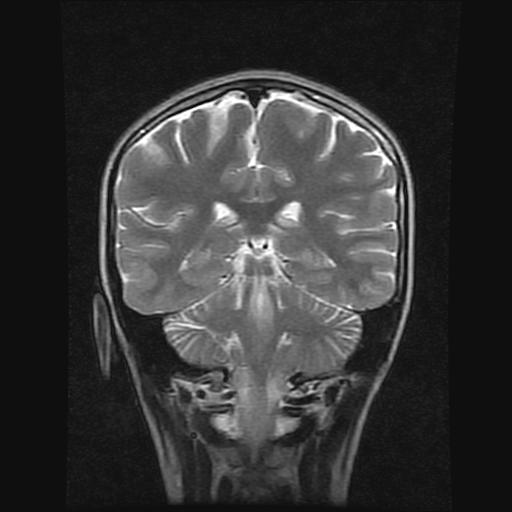

9岁女孩,三岁时诊断为癫痫,一直服丙戊酸钠,现患者一般情况良好,家长复查核磁片,看能否停药..

巨脑回

未见异常信号灶.

未发现异常信号。